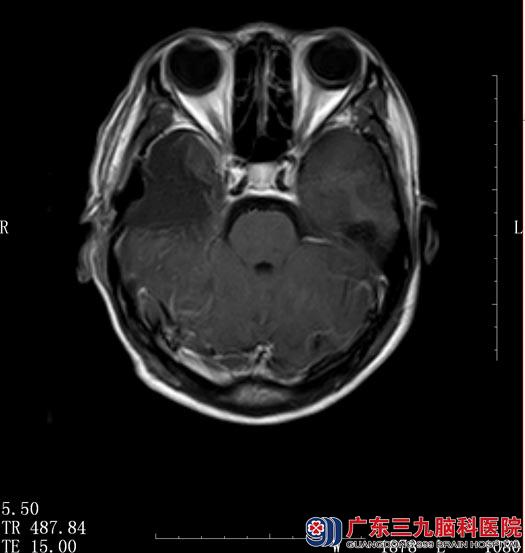

常规术前准备后, 5月11日,鲁明主任主刀在唤醒麻醉下行“右侧颞叶海绵状血管瘤切除+前颞叶切除术”。术中给予电生理监测,脑电图提示右侧颞叶皮质存在异常放电波;麻醉苏醒后,在患者语言及肢体配合下给予全切右侧颞叶海绵状血管瘤,沿右侧颞叶脑电图所示放电范围切除部分颞叶,再次监测皮层,未见异常放电。

术后陈女士未再出现肢体抽搐,四肢活动良好,术后病理结果示“海绵状血管瘤”。

▲手术后